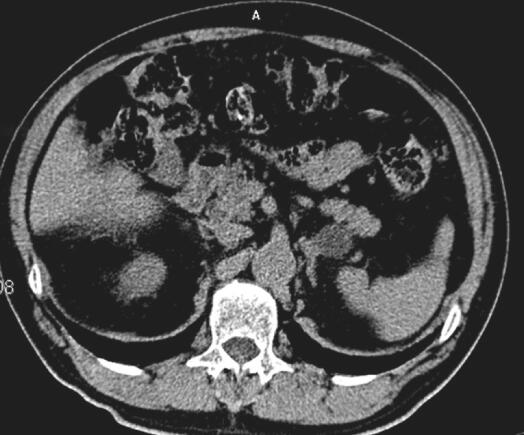

双侧肾上腺CT扫描示:双侧肾上腺区类圆形低密度影,与双侧肾上腺外支分界不清(图1)。双侧肾上腺增强CT扫描:双侧肾上腺区类圆形占位,肿瘤性病变可能:转移瘤?腺瘤?(图2,图3)。

图1 双肾及肾上腺CT:CT示双侧肾上腺腺瘤(箭头标注处)